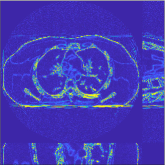

For a 3D cone-beam CT problem, circulant preconditioning is less accurate because the matrix is inherently shift-variant due to the system geometry and/or spatial variations in detector response [44]. Despite this fact, we select a circulant preconditioner to approximate in (4), and solve (2) in 3D CT reconstruction using more PCG inner iterations. The reason is three fold. First, a circulant preconditioner is still one of the classical options to approximate a shift-variant matrix (e.g., ) and accelerate CG (see, for example, [44, 45]). Second, effective learned transforms are generally close to orthogonal (the same applies to the 2D case), and a scaled identity preconditioner can approximate the term . Third, a few PCG iterations in Algorithm 1 can provide fast convergence: 1) Fig. 2 shows that and PCG iterations give very similar convergence rates; 2) in the 3D CT reconstruction, the convergence rates of Algorithm 1 are comparable to those provided in 2D CT reconstruction – see Fig. 5. More sophisticated preconditioners might provide faster convergence [46, 47].

Our main concern in convergence rates of Algorithm 1 lies with an inaccurate preconditioner (e.g., circulant one) particularly for the 3D sparse-view CT reconstructions. To see the effects of using a loose preconditioner in Algorithm 1, we compared the convergence rates of the 3D case with those of 2D (Fig. 5(a) and Fig. 5(b)). In the first iterations, Algorithm 1 converges faster in 2D experiments than 3D experiments. However, after iterations, the convergence rates of Algorithm 1 are similar in both 2D and 3D reconstructions. In addition, more PCG (with a circulant preconditioner) iterations does not significantly accelerate Algorithm 1 (see Fig 2). These empirically observations imply that, in the 3D sparse-view CT reconstructions, Algorithm 1 using a circulant preconditioner ( PCG iterations) is a reasonable choice.